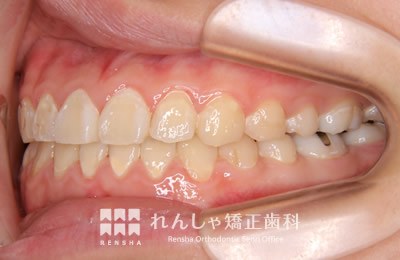

大人

軽度の上顎前突であれば、上奥歯の後方移動で前歯の前突を改善することもありますが、上顎前突は叢生の問題も絡んでいることがほとんどで、永久歯の抜歯が必要になることがあります。また上奥歯の後方移動には矯正矯正用アンカースクリューの併用が効果的です。

治療前

| 主訴 | 出っ歯と前歯のがたつき |

|---|---|

| 診断名 | Angle Class II 上顎前突 |

| 初診時年齢 | 20歳7か月 |

| 装置名 | マルチブラケット装置 矯正用アンカースクリュー |

| 抜歯非抜歯 | 上下顎左右第二小臼歯の抜歯(合計4本) |

| 治療期間 | 3年2か月 |

| 費用の目安 | 約75万円+消費税(検査料金、都度の処置費用等も合わせた総額) |

| リスク副作用 | 歯の移動に伴う軽微な歯根吸収、歯槽骨吸収、歯肉退縮(本症例では軽度の歯肉退縮と歯根吸収を認めた)、矯正器具装着中のカリエスリスク増大(本症例では大臼歯にカリエスが発生し、その後う蝕処置)、上顎左側犬歯の失活 |